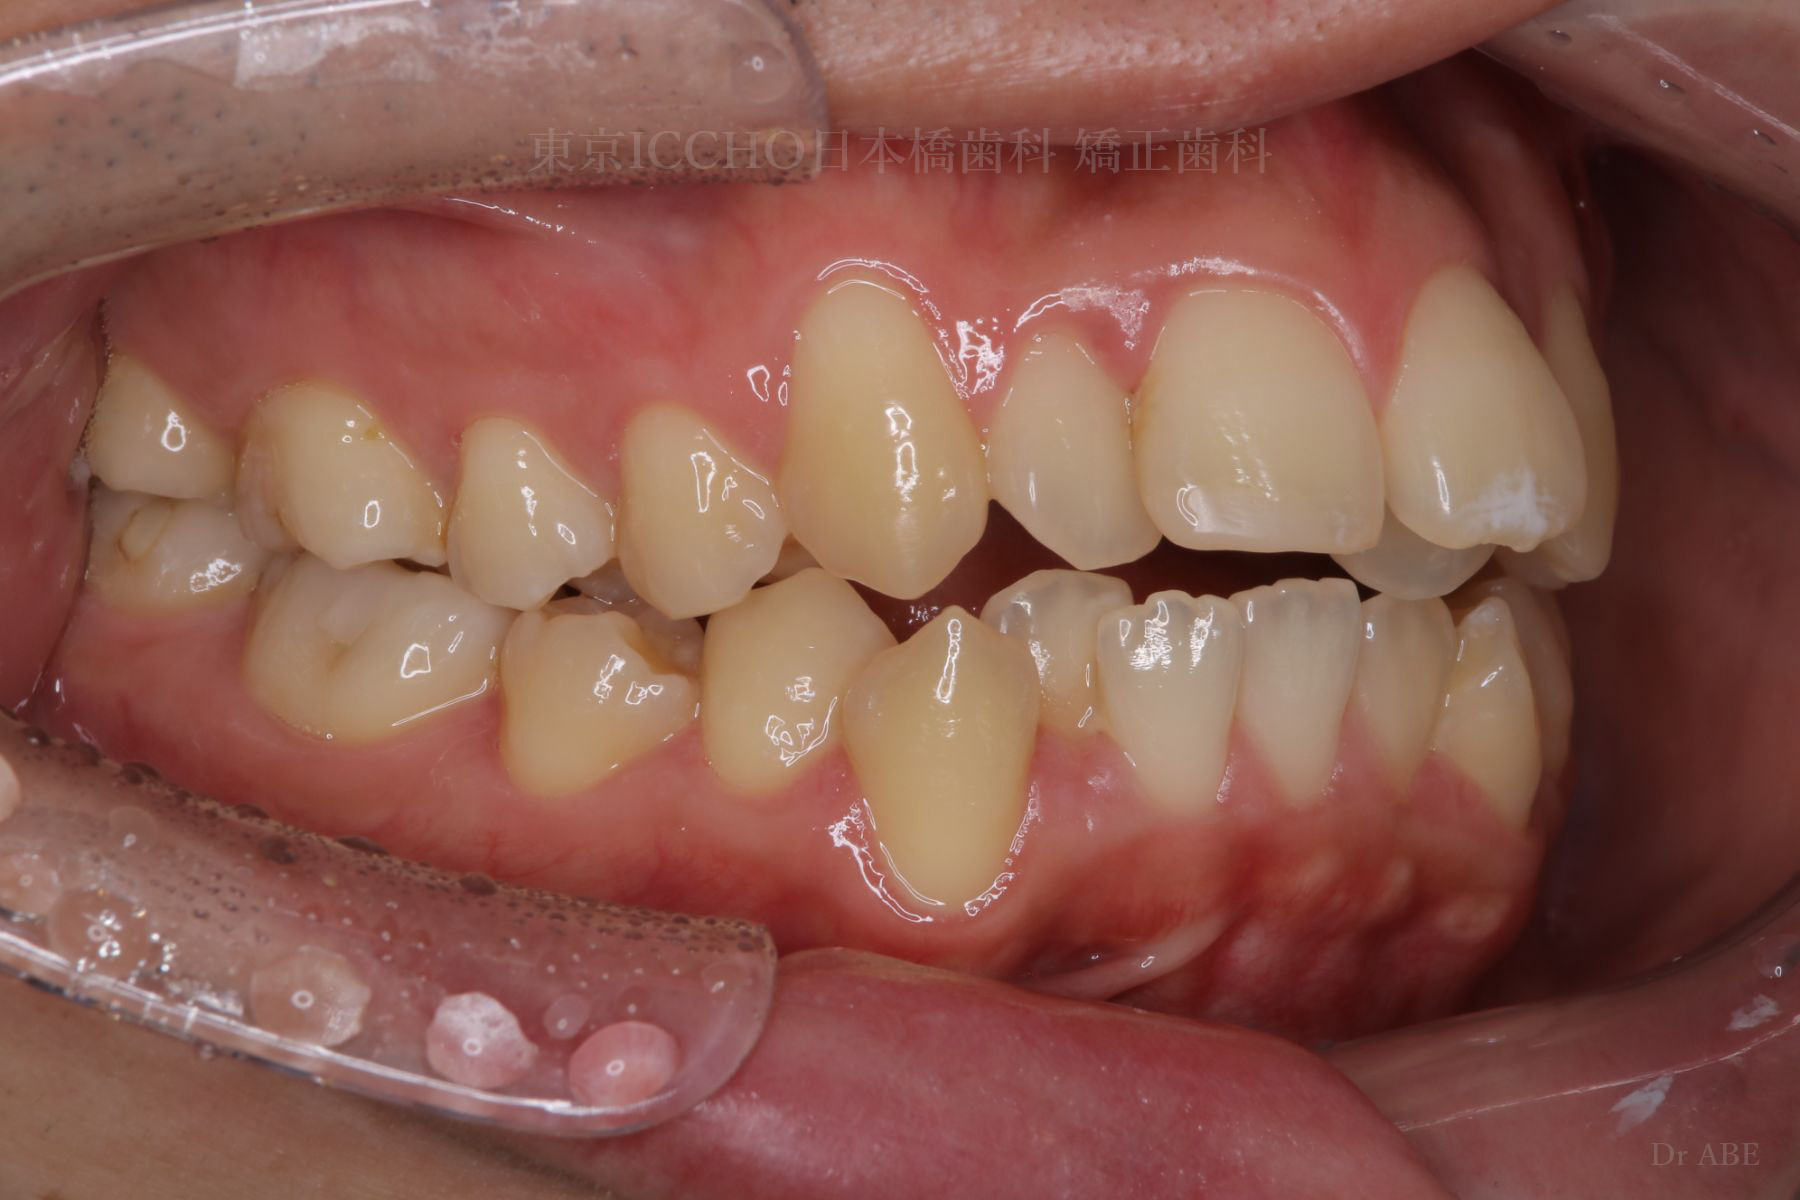

治療前

主訴 前歯が噛めないこと、出ているのを直したい。

治療内容 かみ合わせの不正と顎が小さいため、上下左右第一小臼歯4本の抜歯を行い前歯を後ろへ下げた。

また、前歯が噛まない状態のため、かみ合わせを少し下げて噛むように誘導し、全体的にかみ合わせとして機能的な矯正治療を行った。